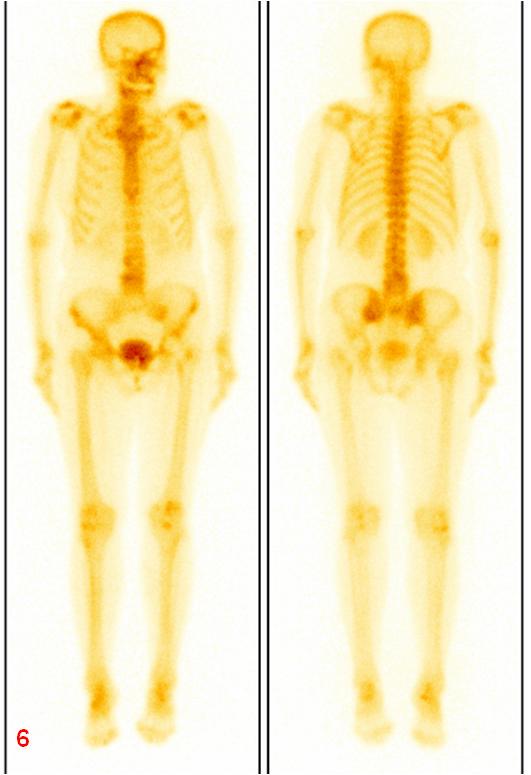

圖6復查ECT雙側(cè)骶髂關(guān)節(jié)、骶骨及左側(cè)恥骨代謝較前明顯減低。